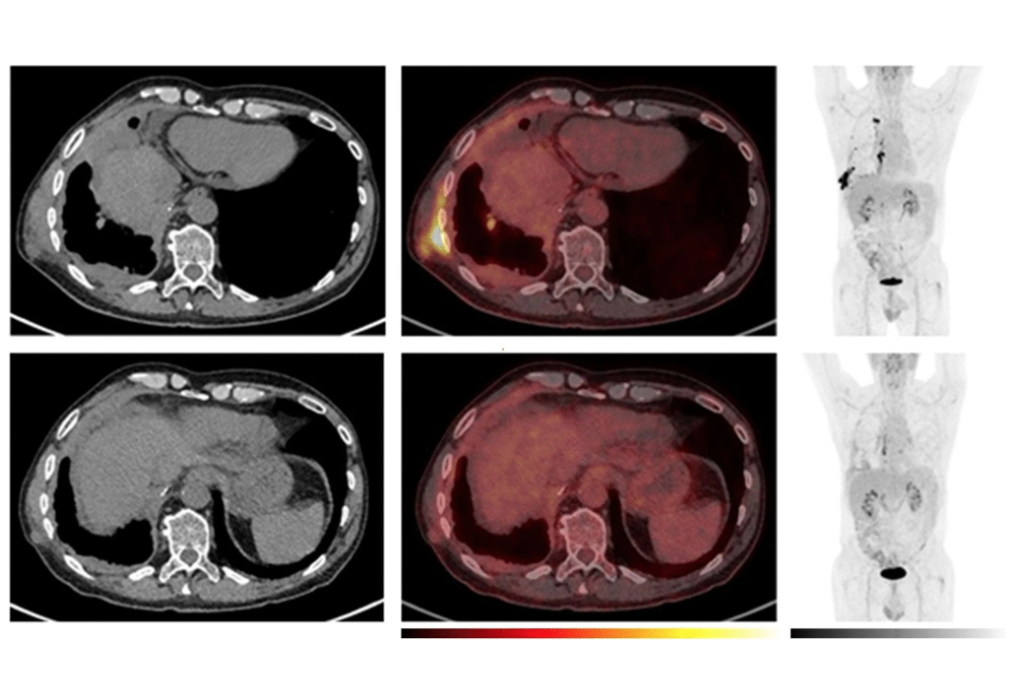

PET/CT provides clarity in pleural mesothelioma cases

Metabolic tumor volume is a relatively accurate predictor of outcomes in pleural mesothelioma treated with immunotherapy, according to a Norwegian-led PET/CT study.